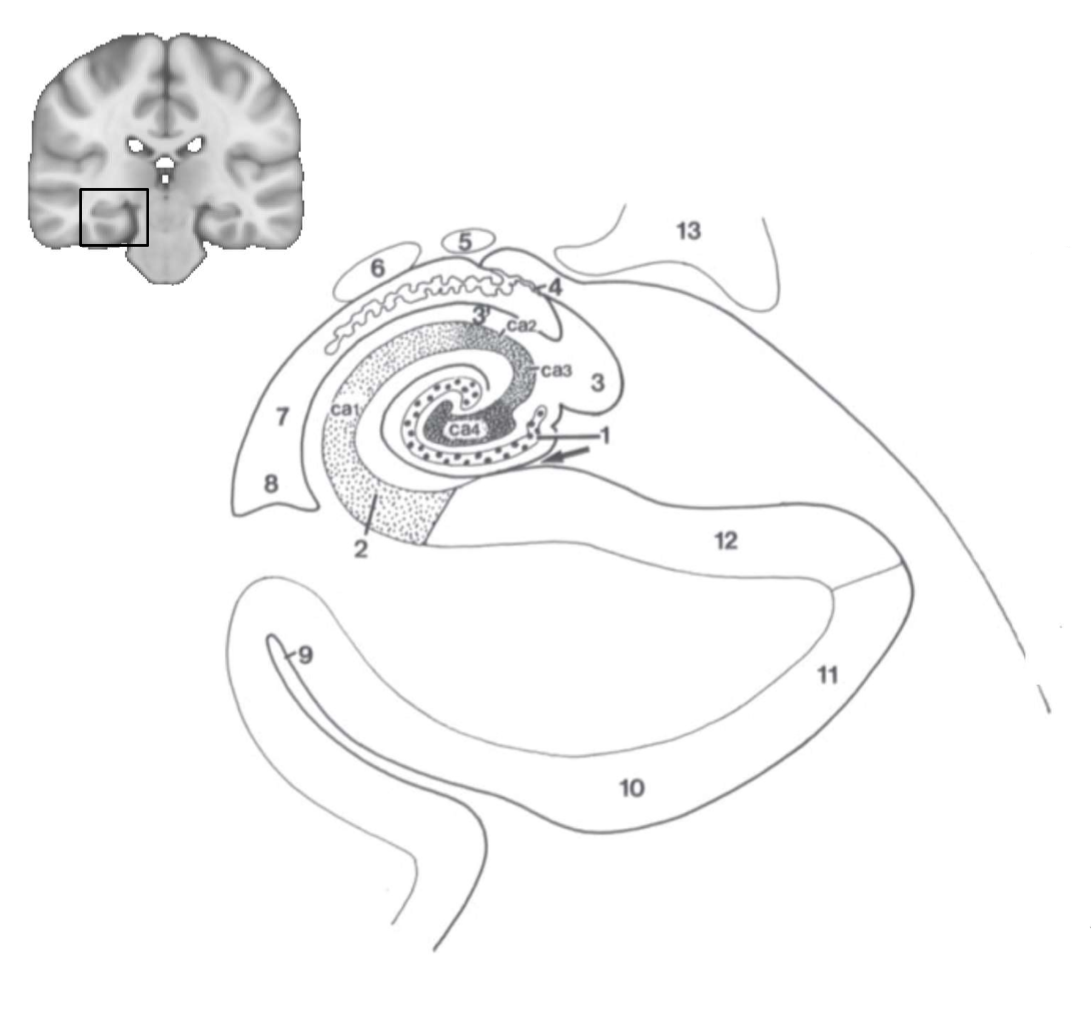

What structure is this?

hippocampus

What is 1?

hippocampus

What is 2?

rhinal sulcus

What is 3?

lateral ventricle

What is 4?

thalamus

What is 5?

entorhinal cortex

What is 6?

perirhinal cortex

What is 7?

parahippocampal cortex

What is 1?

gyrus dentatus

What is 2?

cornu ammonis

What is 3?

fimbria

What is 3’?

alveus

What is the arrow pointing to?

happicampal sulcus

What is ca1, ca2, ca3 and ca4?

fields of cornu ammonis

What is 4?

tela choroidea

What is 5?

stria terminalis

What is 6?

tail of caudate nucleus

What is 7?

temporal horn of lateral ventricle

What is 8?

collateral eminence

What is 9?

collateral sulcus

What is 10?

parahippocampal

What is 11?

entorhinal area

What is 12?

subiculum

What is 13?

lateral geniculate body